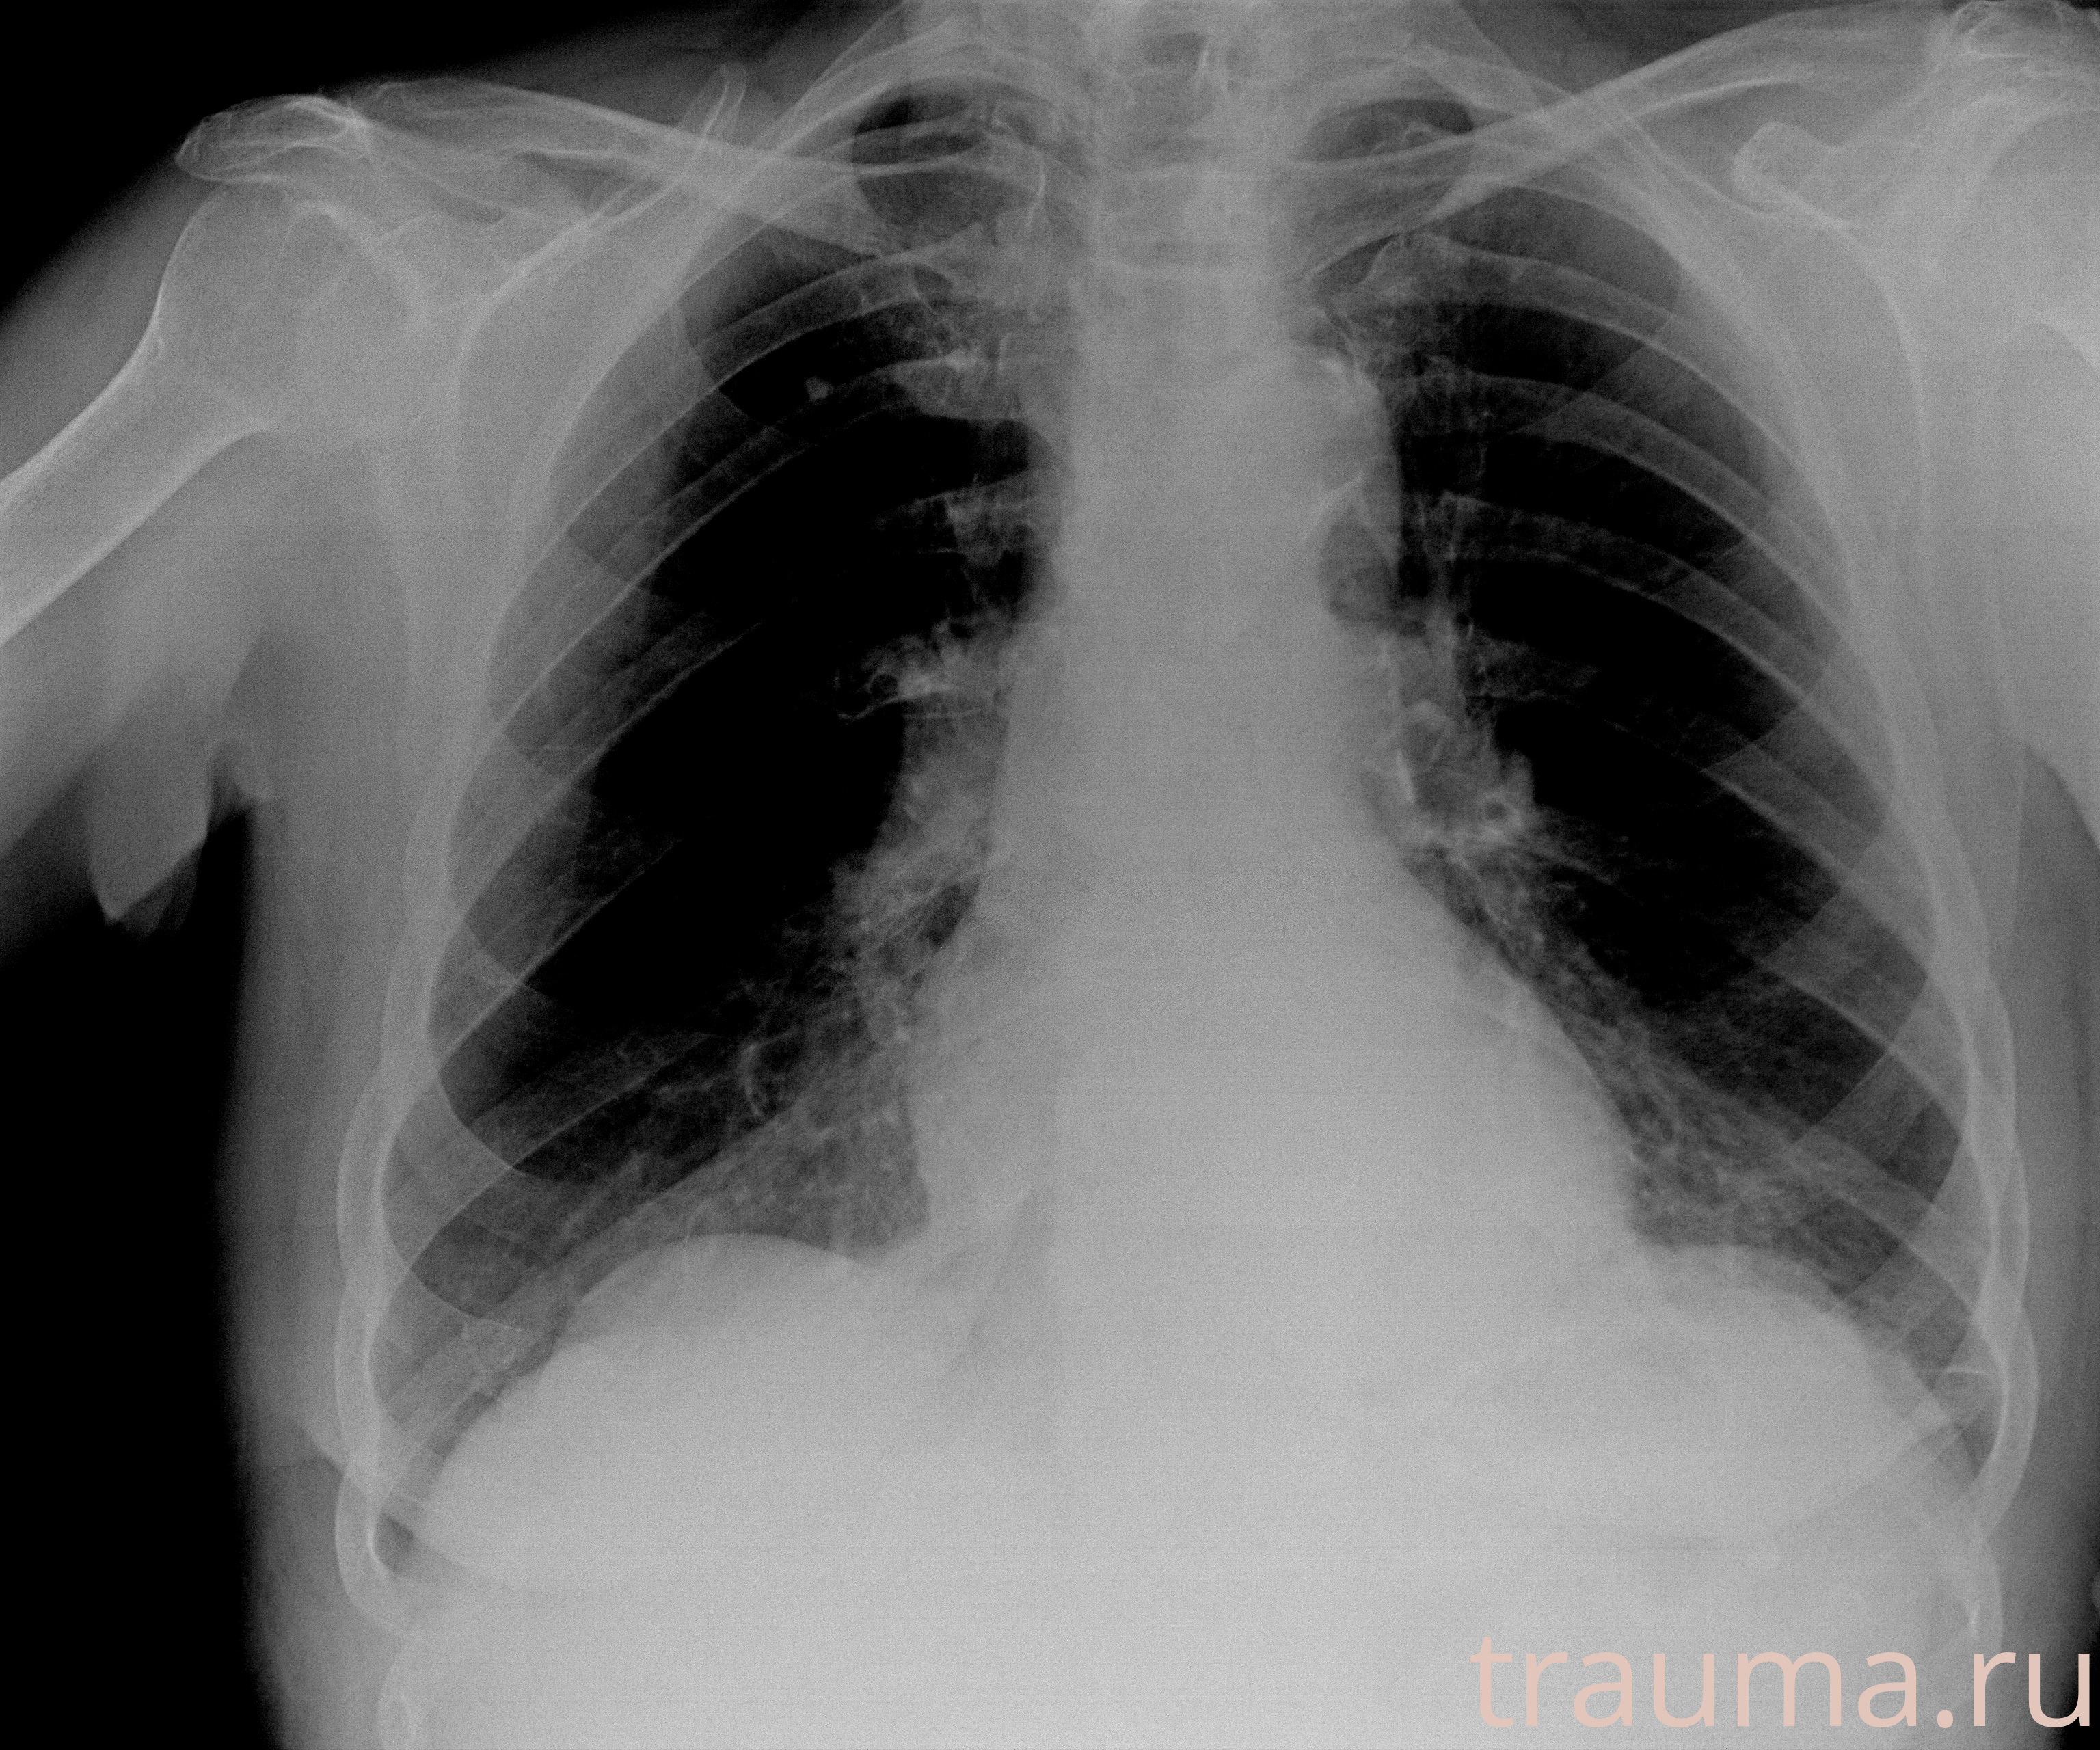

Рентгенограммы